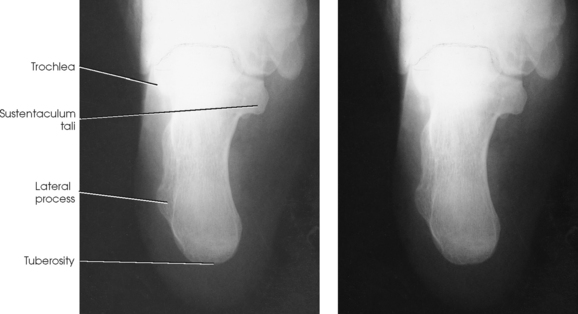

The calcaneus is the largest and strongest tarsal bone (Fig. 6-3). Some texts refer to it as the os calcis. It projects posteriorly and medially at the distal part of the foot. The long axis of the calcaneus is directed inferiorly and forms an angle of approximately 30 degrees. The posterior and inferior portions of the calcaneus contain the posterior tuberosity for attachment of the Achilles tendon. Superiorly, three articular facets join with the talus. They are called the anterior, middle, and posterior facets. Between the middle and posterior talar articular facets is a groove, the calcaneal sulcus, which corresponds to a similar groove on the inferior surface of the talus. Collectively, these sulci constitute the sinus tarsi. The interosseous ligament passes through this sulcus. The medial aspect of the calcaneus extends outward as a shelflike overhang and is termed the sustentaculum tali. The lateral surface of the calcaneus contains the trochlea.

The talus, irregular in form and occupying the superiormost position of the foot, is the second largest tarsal bone (see Figs. 6-1 to 6-3). The talus articulates with four bones—tibia, fibula, calcaneus, and navicular bone. The superior surface, the trochlear surface, articulates with the tibia and connects the foot to the leg. The head of the talus is directed anteriorly and has articular surfaces that join the navicular bone and calcaneus. On the inferior surface is a groove, the sulcus tali, that forms the roof of the sinus tarsi. The inferior surface also contains three facets that align with the facets on the superior surface of the calcaneus.

Each of the three parts of the subtalar joint is formed by reciprocally shaped facets on the inferior surface of the talus and the superior surface of the calcaneus. Study of the superior and medial aspects of the calcaneus (see Fig. 6-3) helps the radiographer to understand better the problems involved in radiography of this joint.